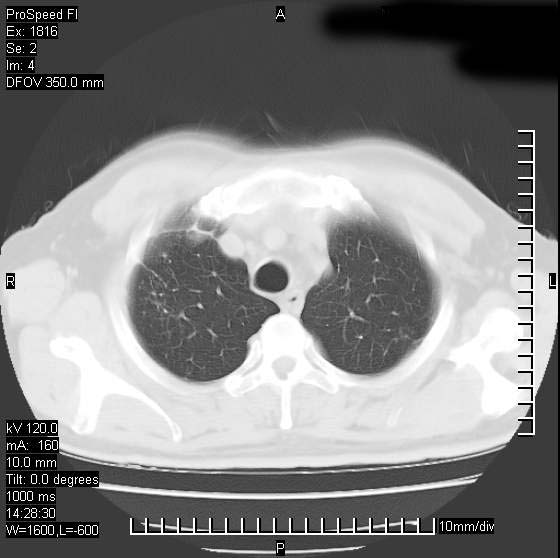

男性,50 ,肺结核9年,咳嗽,胸痛一周。右上肺见一厚壁空洞,周边有点样钙化,胸膜牵拉,洞壁较光整。诊断结核性空洞。有癌性的可能吗? 余肺野无异常,没有上传。

不像是肺ca倒更像一个结核空洞,因为看一下他内前方的支气管一点没有浸润征象只是压迫.

洞壁较厚内壁比较光整,两个病灶有关联性,纵隔淋巴结不大,考虑结核性空洞。

结核有可能,肺癌待排。空洞的前上还方见一软组织结节影。

部分层面见空洞为近似新月形,洞壁内缘尚规整且近肺门侧,周围见索条影、卫星灶,结合病史,首先考虑肺tb可能大。

右肺上叶为两个病灶,前面为陈旧型结核灶,其后方病灶像肺脓肿